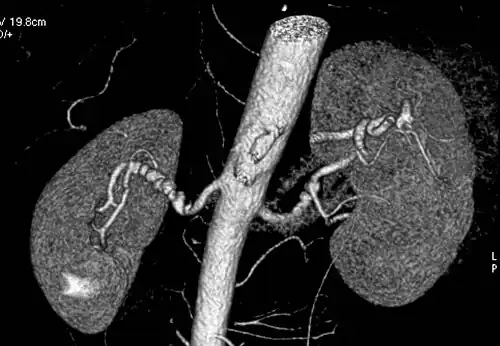

Renal arteries

Visualization of blood flow in the renal arteries (those supplying the kidneys) in patients with high blood pressure and those suspected of having kidney disorders can be performed using CTA. Stenosis (narrowing) of a renal artery is a cause of hypertension (high blood pressure) in some patients and can be corrected. A special computerized method of viewing the images makes renal CT angiography a very accurate examination.[6] CTA is also used in the assessment of native and transplant renal arteries.[3] While CTA is great for imaging of the kidneys, it lacks the ability to perform procedures at the same time. Thus traditional catheter angiography is used in cases of acute renal hemorrhage or acute arterial obstruction.[2]